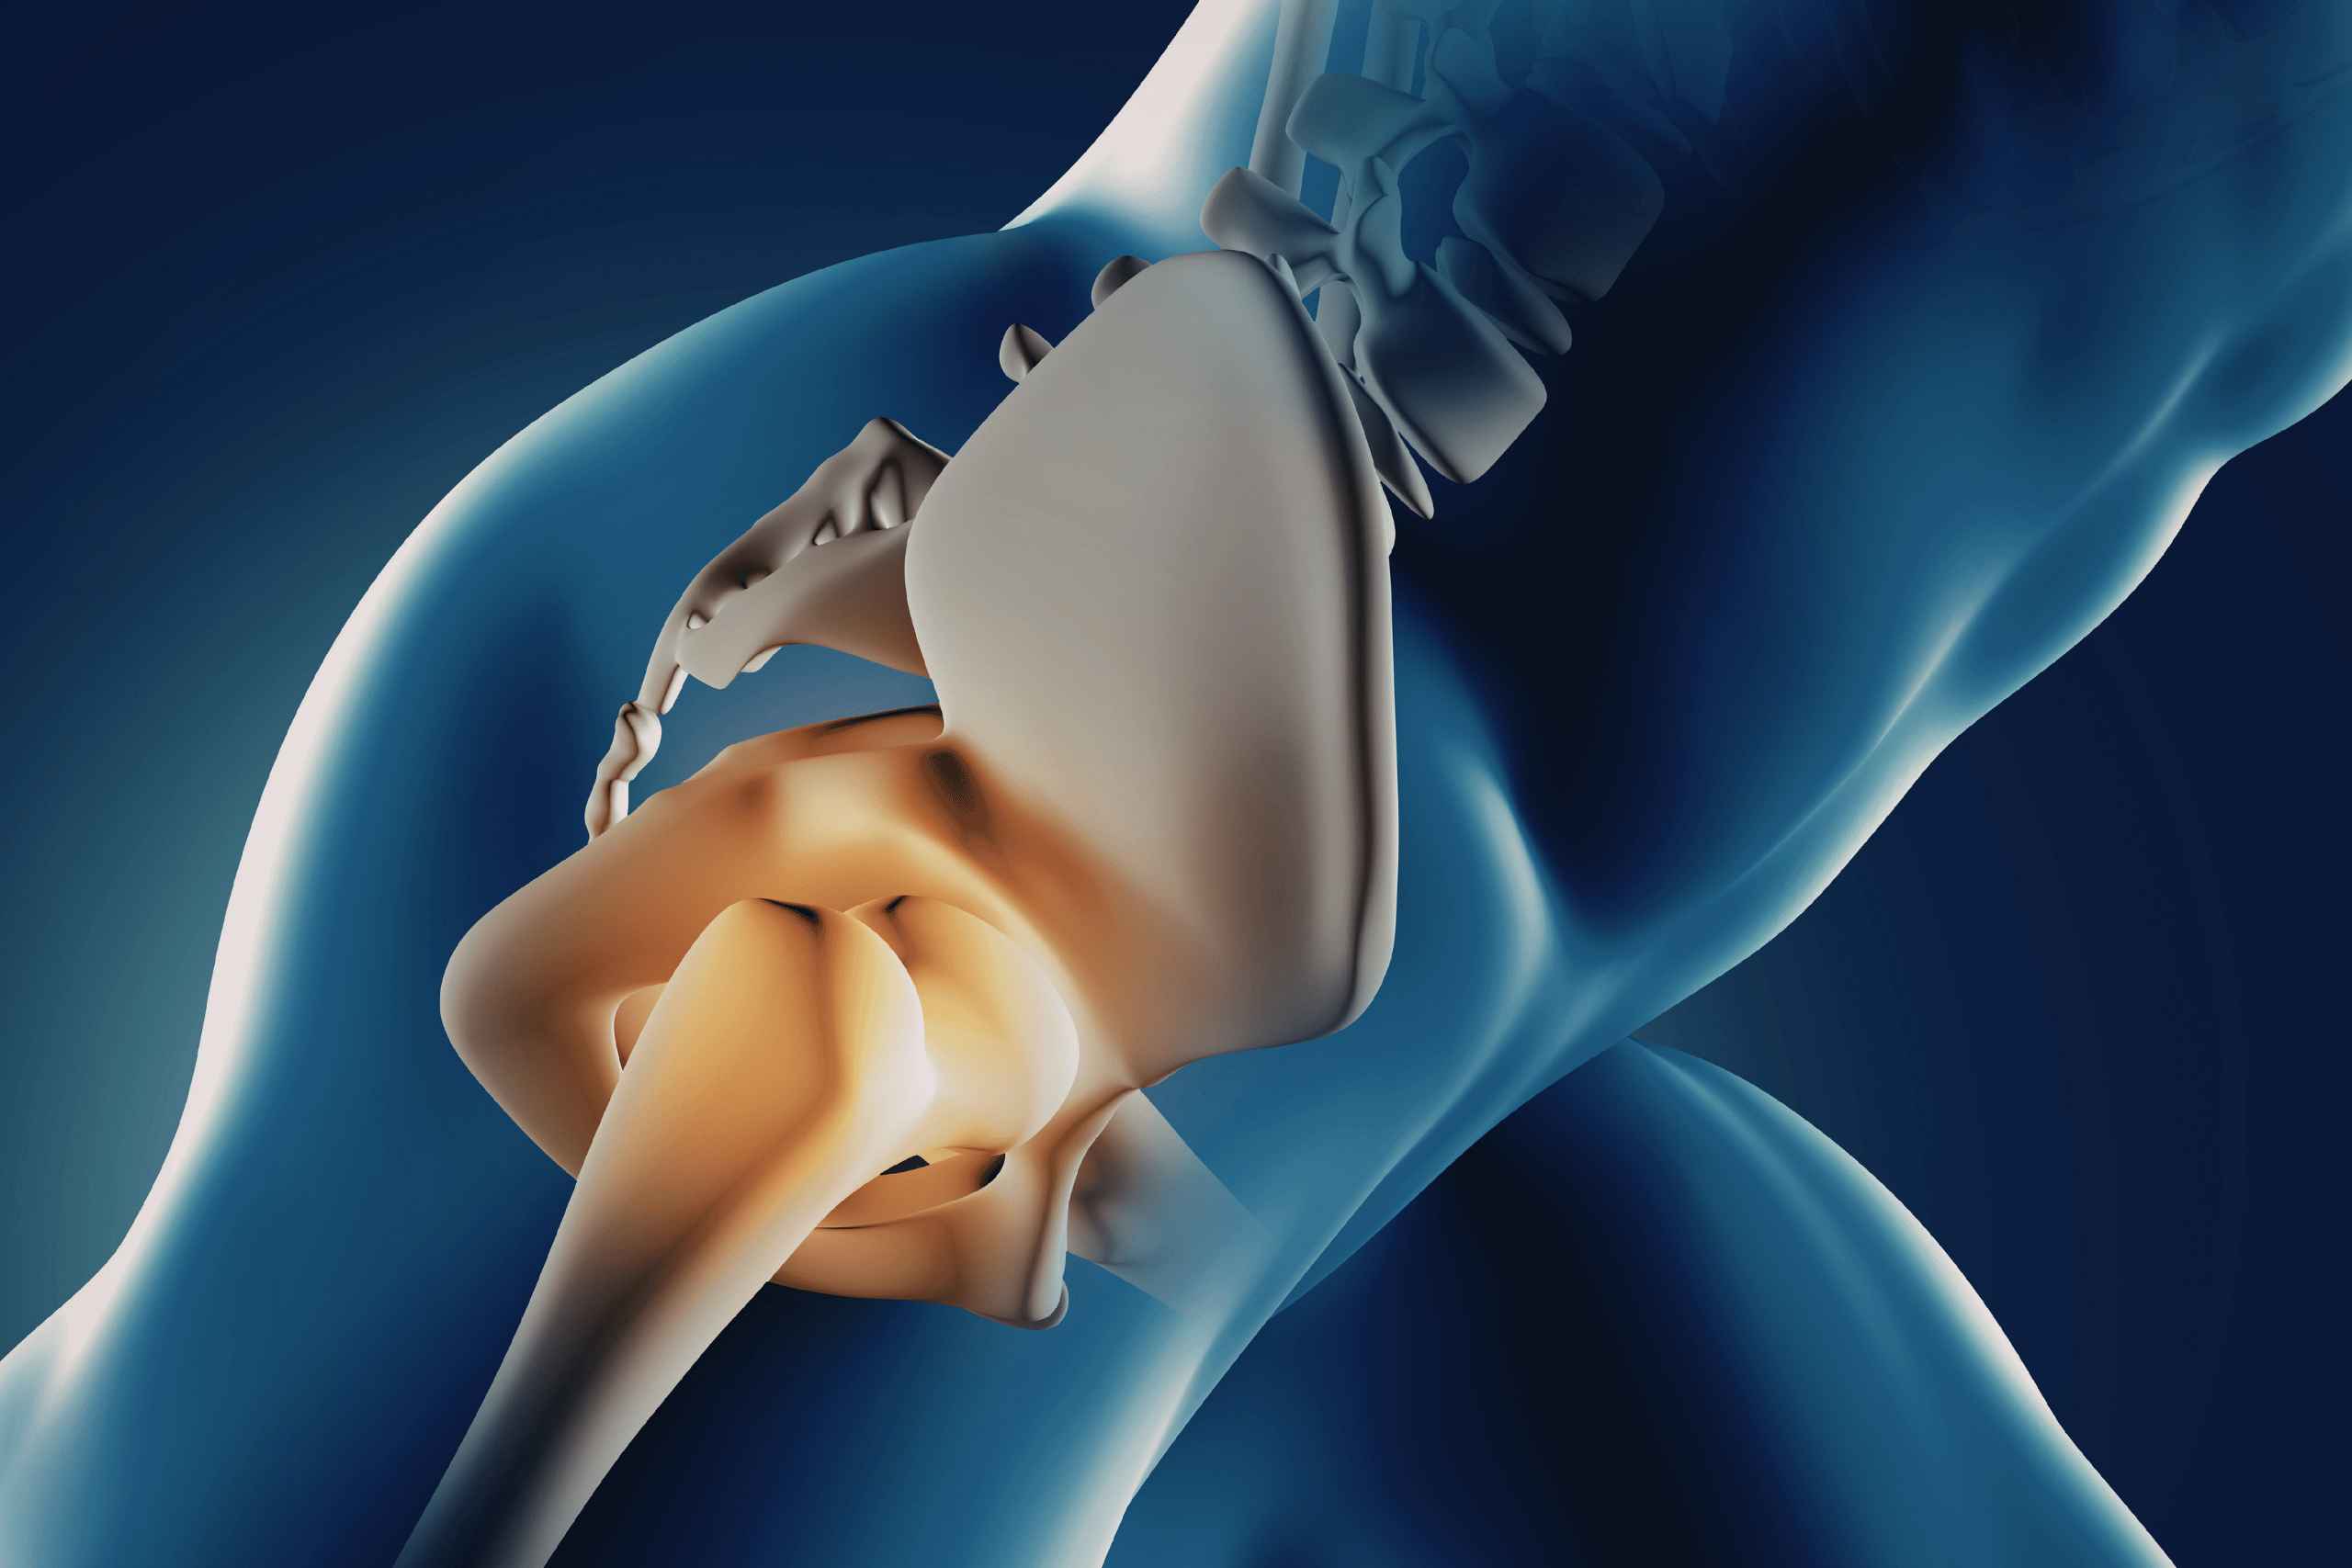

I had been suffering from severe knee pain for more than two years. After consulting the doctors at Vale Specialty Ortho Clinic, I finally found the right diagnosis and treatment. The doctors explained everything clearly and the care from the staff was excellent. Today I can walk comfortably again. Thank you to the entire Vale team for their wonderful support.